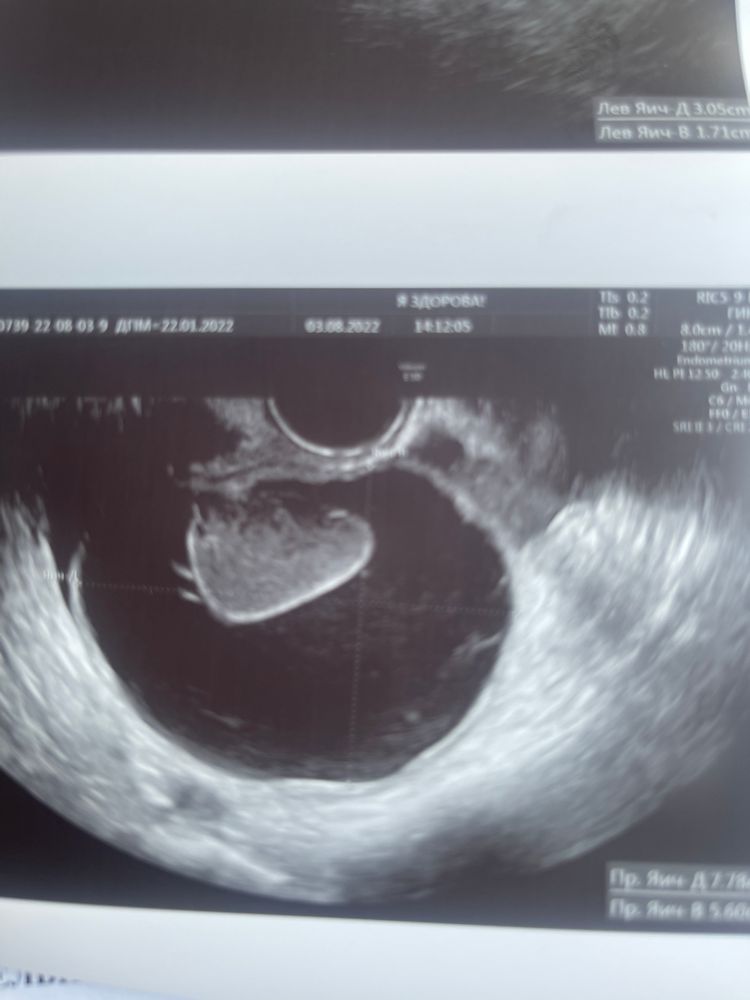

Киста жт или фолликулярная, по фото!))

Сегодня на 24дц пошла глянуть, к другой узистке. Она меня ошарашила кистой ЖТ 5см. Сказала, что точно не фолликулярная!

Читала тут, что некоторые по внешнему виду кисты и яичника понимают, киста жт это или фолликулярная. Глянете?

Серая - это ЖТ. О после укола в среднем через 36-48 часов если что.

Если 5см, то фолликулярная

Серая - это ЖТ, а у вас она черная, значит фолликулярная

L.N.M, киста жт может быть до 8см, как пишут в интернетах)

а на фото она разве не серая? Или я не туда смотрю?)